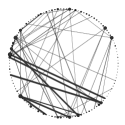

|

| (a) early AD patients | (b) controls |

We apply in the AD case the same network analysis strategy as in the PD experiment inferring for both cases and controls 51 selected pathways for early stage AD and 34 for late stage AD. The full list of reconstructed pathways is reported in Table 10.2.3. In Table 3 we summarize the main findings discussed hereafter.